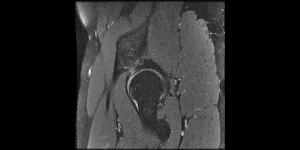

Infelizmente, devido aos impactos causados pelos chutes fortes, ele acabou desenvolvendo uma lesão grave nos quadris. O que fez com que acabasse sentindo cada vez mais dor ao treinar e dar aulas. As dores fizeram com que ele precisasse abrir mão de seu sonho. E mesmo parando com os treinos, ainda sente muita dor, o que acaba prejudicando seu trabalho, devido as posições necessárias para o serviço. E também seu dia a dia em casa, com a família e na hora de dormir porque as dores permanecem o tempo todo.

O único jeito de fazer essa dor passar, e também prevenir para que o quadro não piore ainda mais, é uma cirurgia. Que financeiramente não está ao nosso alcance, mas precisa ser feita o mais rápido possível.